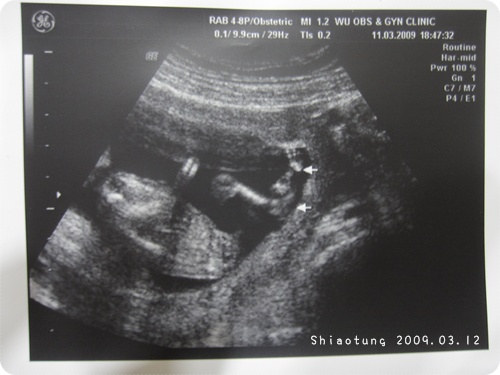

因此這回超音波,

有特地給我一張手和一張腳的照片,

於是醫生還是很認真的每一根細手細腳都找出來給我看。

醫生又講說:像到妳這時候可以看到手腳揮動,

但是這時期如果都沒看到,再大的話寶寶手腳也可能都會被壓住看不清楚。